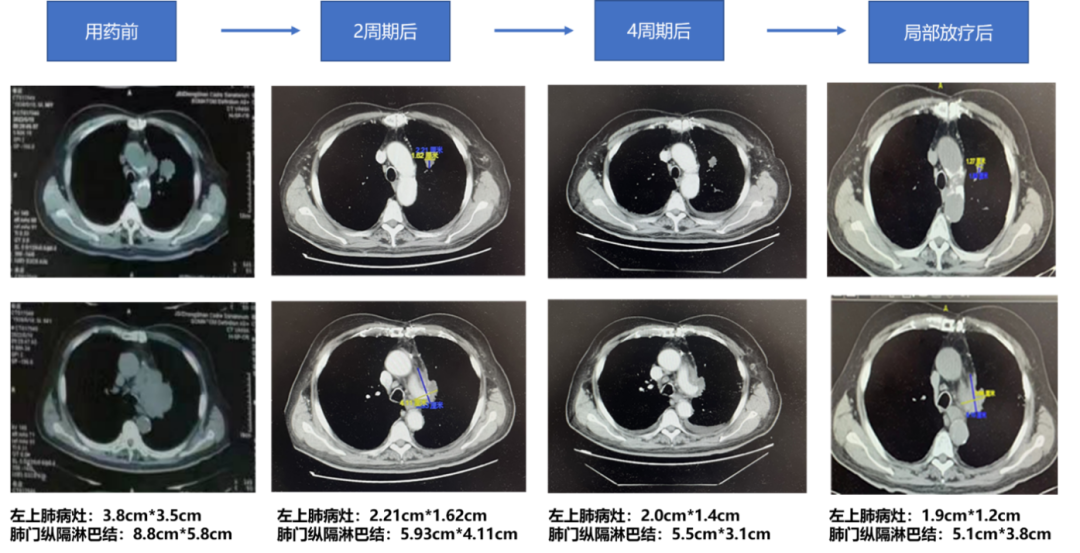

2022-08-12(2周期后)胸部CT:左肺上叶分叶状结节,较前稍缩小,现约1.62cm*2.21cm。左肺门、纵隔见多发大小不等淋巴结,部分有融合,形成不规则软组织肿块,包绕临近血管,较大截面约5.93*4.11cm;两肺肺气肿、肺大泡;两肺散在少许索条,胸膜下为主,呈间质性改变。两肺多发小结节影,较大一枚约0.78cm;双侧锁骨上小淋巴结。两侧未见明显胸腔积液。

2022-09-27(4周期后)胸部CT:左肺上叶分叶状结节,较前稍缩小,现约1.42*2.0cm;左肺门稍肿大淋巴结,较前稍饱满,现约2.71*1.92cm。纵隔多发大小不等淋巴结,部分有融合,形成不规则软组织肿块,包绕临近血管,较大一处现约5.54*3.12cm,前约5.93*4.11cm,较前稍缩小。双侧锁骨上小淋巴结,变化不大。两肺肺气肿、肺大泡,两肺散在斑片索条影,胸膜下为主,呈间质性改变,较前明显;两肺散在小结节影,较大一枚仍0.78cm,变化不大。两侧胸腔少量积液,较前稍增多。

2022-11-10(放疗后)胸部CT:左肺上叶分叶状结节,较前稍缩小,现约1.89*1.27cm,原约1.42*2.0cm;左肺门稍肿大淋巴结,较前相仿,现仍约2.71*1.92cm。纵隔多发大小不等淋巴结,部分有融合,形成不规则软组织肿块,包绕临近血管,较大一处现约5.1*3.86cm,原约5.54*3.12cm,较前稍缩小。双侧锁骨上小淋巴结,变化不大。两肺肺气肿、肺大泡;两肺散在斑片索条影,胸膜下为主,呈间质性改变,较前稍改善。右肺中叶新增实性结节,约0.98*0.9cm;两肺散在小结节影,较大一枚仍约0.78cm,变化不大。两侧胸腔少量积液,较前减少。